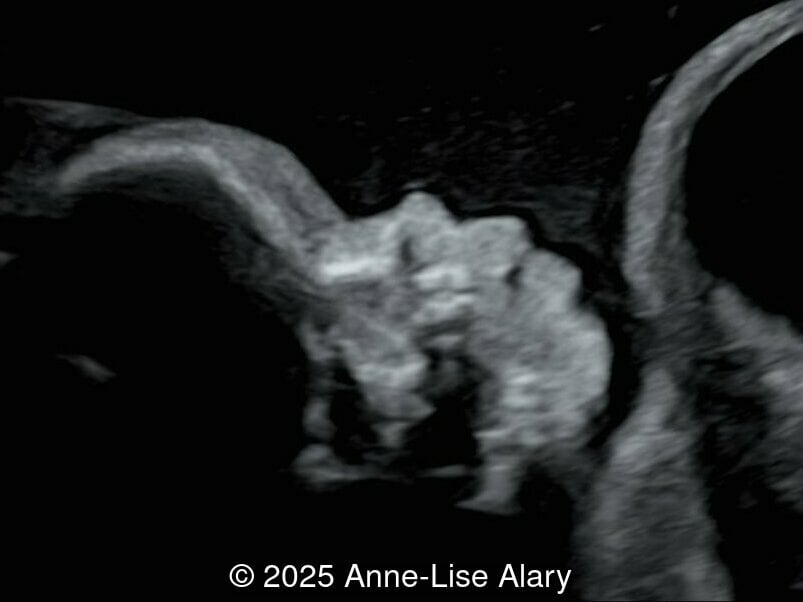

Our prenatal ultrasound revealed a male fetus with megabladder, dilation of both ureter and kidneys, and thinned kidney parenchyma consistent with Lower Urinary Tract Obstruction (LUTO). Additional findings suspected on ultrasound and confirmed on computed tomography included:

- Short long bones (<1st percentile), normal mineralization, and no sign of lethal chondrodysplasia

- Evidence of Potter's sequence due to the lower urinary tract obstruction with small thorax compared to the abdomen, hyperextended neck, and pes varus.

- Dysostosis: Hemivertebrae L3, fused L4-L5, abnormal left foot with short metatarsals and missing phalanges